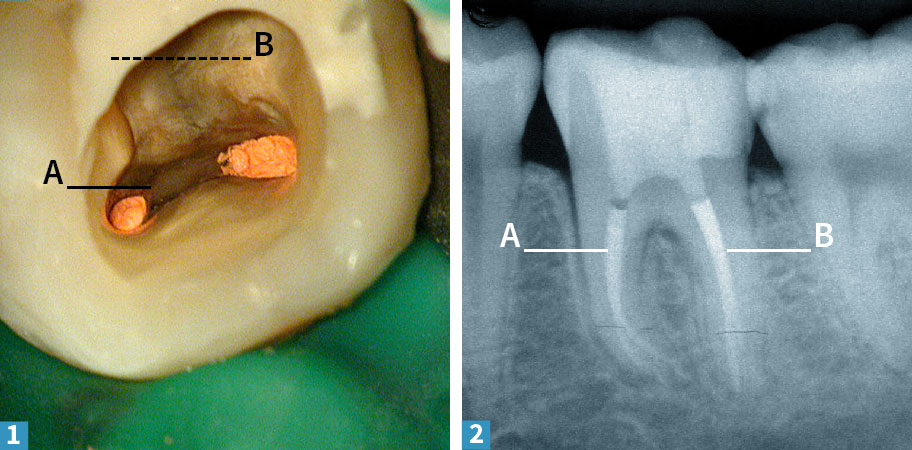

1 Dann werden die beiden schmalen Kanäle der einen Wurzel (A) versorgt.

2 In der Abschlußröntgenaufnahme erkennt man die beiden Stifte in der einen Wurzel, wer genau hinschaut sieht auch in der anderen Wurzel einen separaten, schmalen Abzweig neben der breiteren Füllung. Um den Erhalt des Zahnes mittelfristig zu sichern, wird der Zahn mit einer stabilen, ans Zahnbein geklebten Aufbaufüllung aus Kunststoff versorgt. Die Behandlung ihres Zahnes in unserer Praxis ist damit abgeschlossen. In der Nachsorge sollte der Zahn frühestens ein halbes Jahr nach der Behandlung noch einmal angeschaut werden. Gerne übernehmen wir diese Aufgabe, im Zweifelsfall kann aber auch Ihr Hauszahnarzt die Nachkontrolle übernehmen.